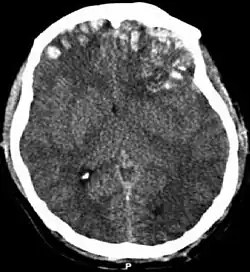

One type of focal injury, cerebral laceration, occurs when the tissue is cut or torn.[37] Such tearing is common in orbitofrontal cortex in particular, because of bony protrusions on the interior skull ridge above the eyes.[31] In a similar injury, cerebral contusion (bruising of brain tissue), blood is mixed among tissue.[23] In contrast, intracranial hemorrhage involves bleeding that is not mixed with tissue.[37]

Hematomas, also focal lesions, are collections of blood in or around the brain that can result from hemorrhage.[11] Intracerebral hemorrhage, with bleeding in the brain tissue itself, is an intra-axial lesion. Extra-axial lesions include epidural hematoma, subdural hematoma, subarachnoid hemorrhage, and intraventricular hemorrhage.[38] Epidural hematoma involves bleeding into the area between the skull and the dura mater, the outermost of the three membranes surrounding the brain.[11] In subdural hematoma, bleeding occurs between the dura and the arachnoid mater.[23] Subarachnoid hemorrhage involves bleeding into the space between the arachnoid membrane and the pia mater.[23] Intraventricular hemorrhage occurs when there is bleeding in the ventricles.[38]

Movement disorders that may develop after TBI include tremor, ataxia (uncoordinated muscle movements), spasticity (muscle contractions are overactive), myoclonus (shock-like contractions of muscles), and loss of movement range and control (in particular with a loss of movement repertoire).[93][154] The risk of post-traumatic seizures increases with severity of trauma and is particularly elevated with certain types of brain trauma such as cerebral contusions or hematomas.[145] People with early seizures, those occurring within a week of injury, have an increased risk of post-traumatic epilepsy (recurrent seizures occurring more than a week after the initial trauma).[155] People may lose or experience altered vision, hearing, or smell.[11]